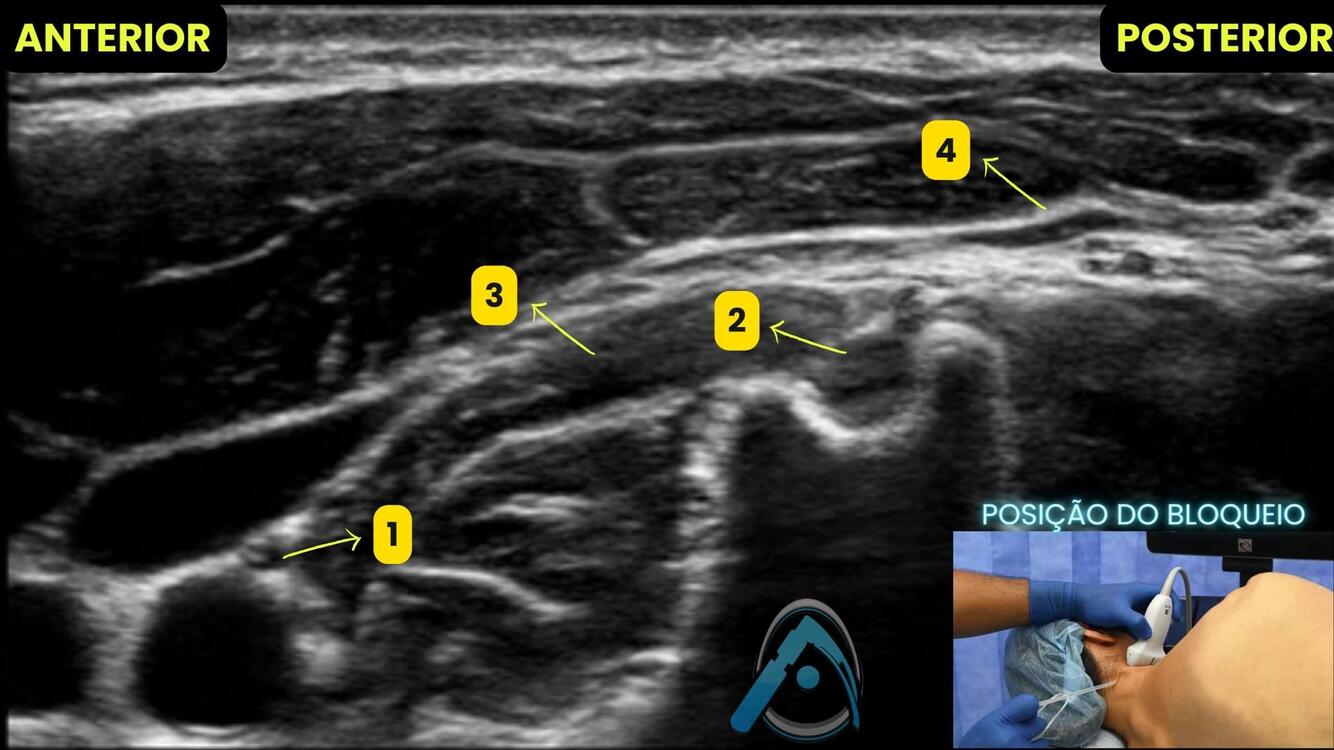

Q

Identificar as estruturas do bloqueio do plexo cervical abaixo:

A

1. n. Vago

2. C4

3. m longo da cabeça

4. Fascia cervical profunda